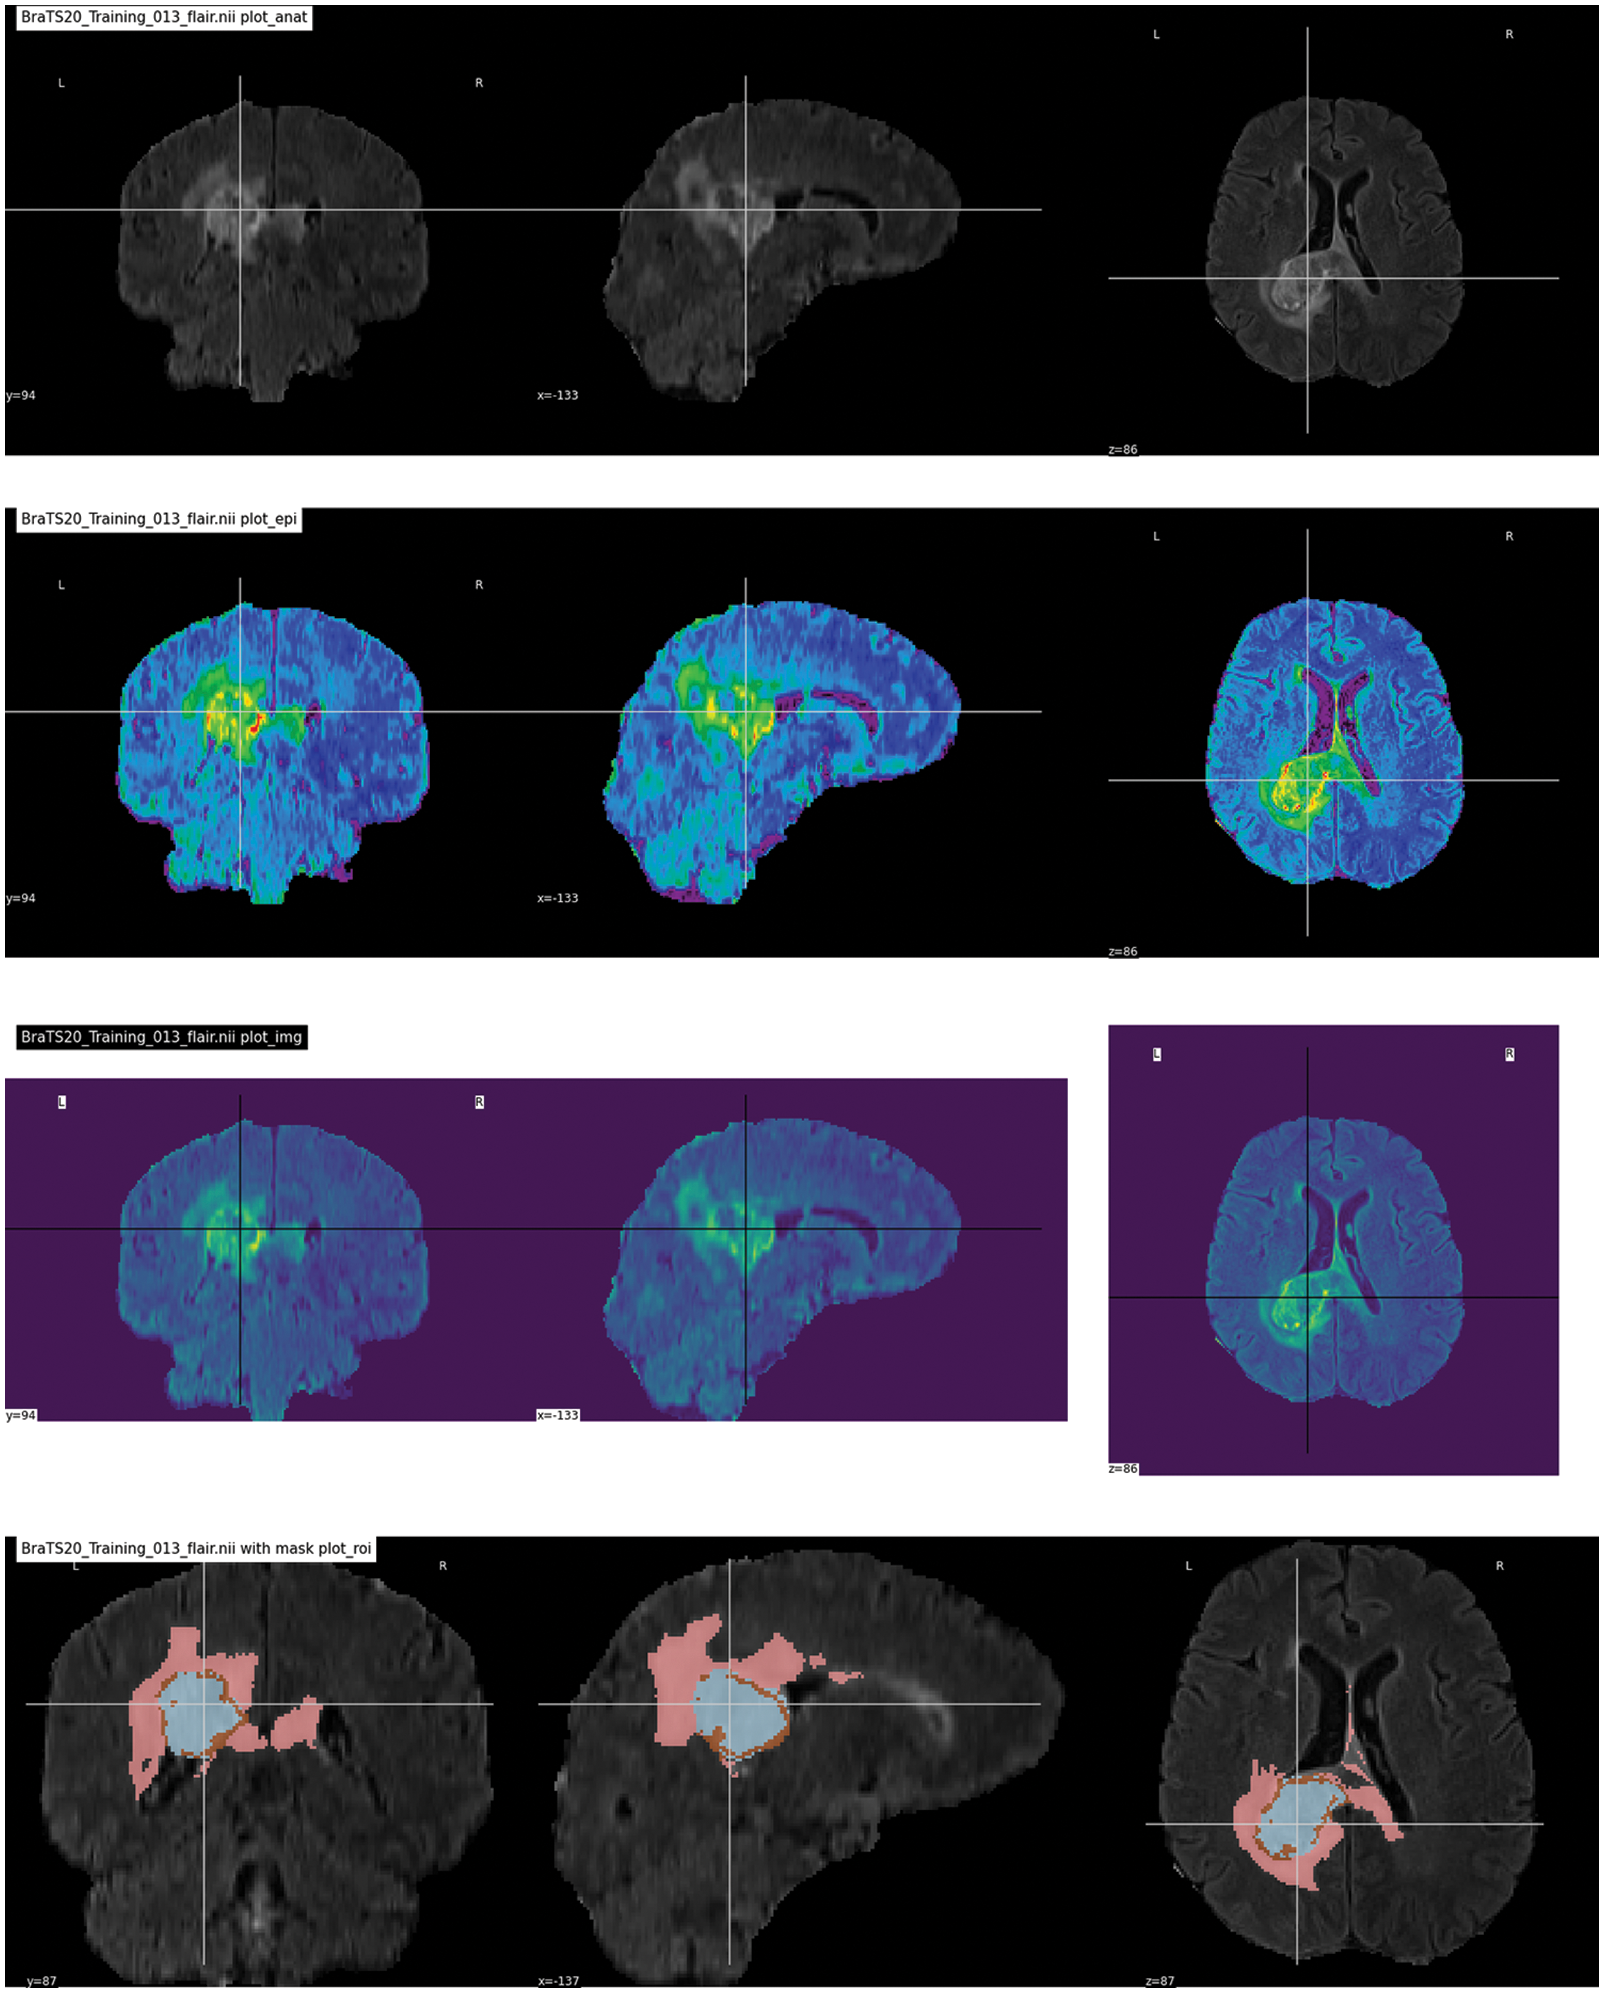

The brain tumor segmentation 2020 (BraTS2020) used for this research is publicly available https://www.kaggle.com/datasets/awsaf49/brats20-dataset-training-validation. It consists of different image folders such as training 249, validation 74, and testing 45. Each folder contains five NIfTI files (Flair, T1, T1ce, T2, and Seg). Each file contains 155 slices of image. Some data samples are shown in Fig. 7. In the preprocessing phase, the noise was removed from the images, the images were resized, and duplicates were removed. Overall, the dataset was separated into testing, training, and validation sets in ratios of 15%, 70%, and 15%, respectively. The dataset details are given in Tab. 2, along with the distribution.

Figure 7: Dataset sample images